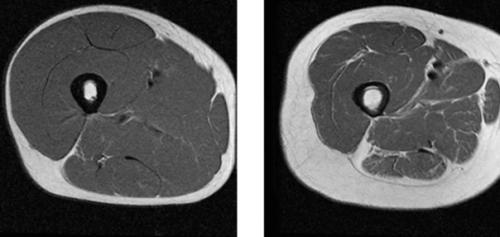

Слева на разрезе - здоровое тело, справа - с дефицитом мышечной массы, который называется саркопенией.

На самом деле, сейчас у многих женщин как справа на разрезе с подросткового возраста уже.